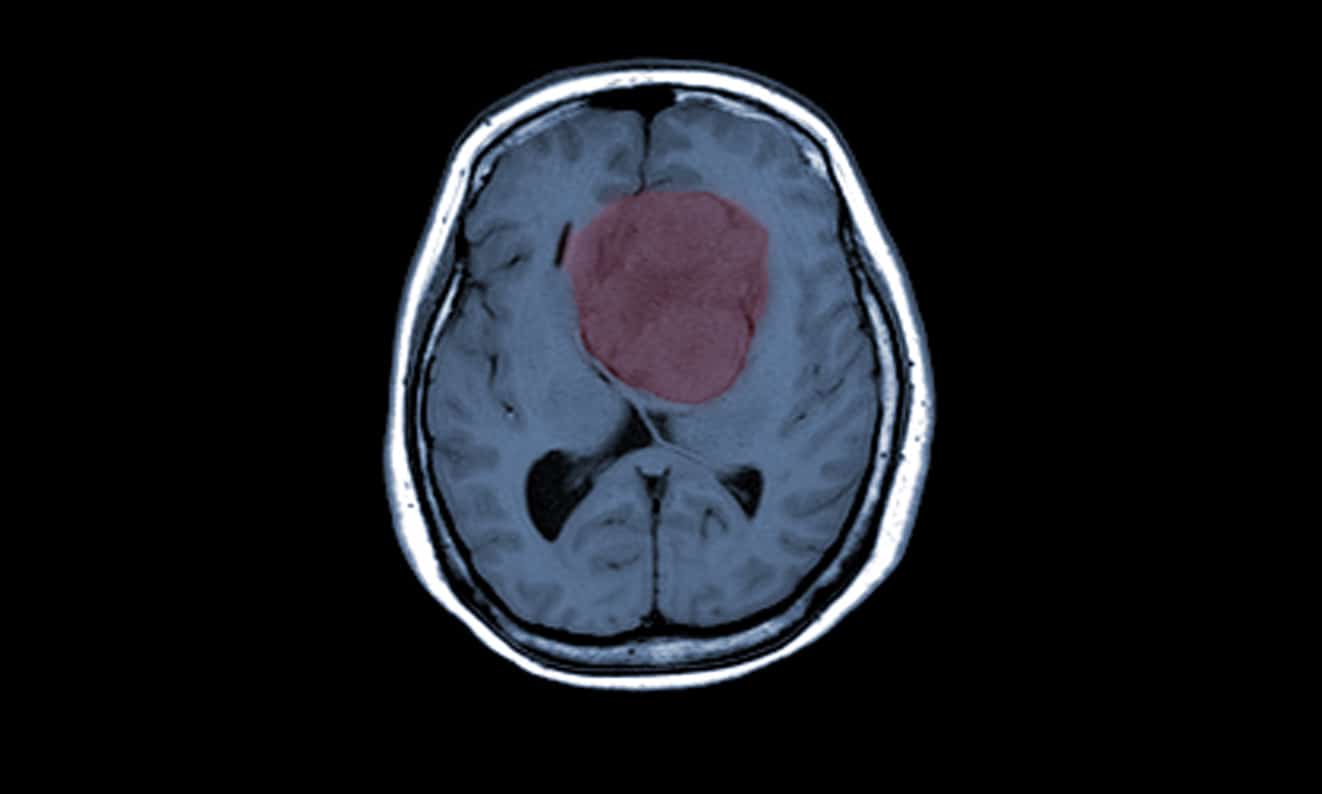

6. Chẩn đoán u màng não

U màng não hiếm khi được phát hiện sớm trước khi xuất hiện triệu chứng.

Nếu có dấu hiệu nghi ngờ khối u, bác sĩ có thể chỉ định chụp MRI và/hoặc CT scan để xác định vị trí và kích thước của khối u.

MRI có thể xác định u màng não là lành tính hay ác tính không?

Chụp MRI và CT scan có thể giúp phân biệt u màng não lành tính hay ác tính. Tuy nhiên, sinh thiết phẫu thuật vẫn là phương pháp chính xác nhất để xác định bản chất của khối u.